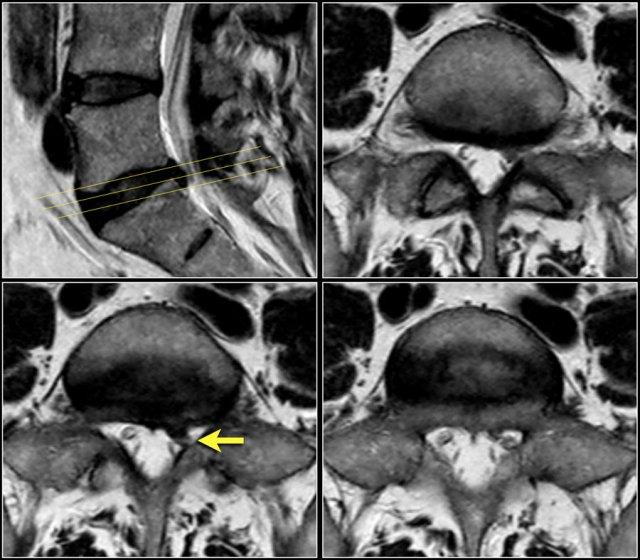

Tốt hơn nên sử dụng các lát cắt liên tục với cùng một góc nghiêng, song song với tầng nghi ngờ có chèn ép thần kinh.

Cách này có ưu điểm là cho phép theo dõi toàn bộ đường đi của rễ thần kinh liên quan qua bốn tầng có thể xảy ra chèn ép.

Khi khảo sát nhiều tầng với các góc nghiêng khác nhau như trong ví dụ bên phải, sẽ không thể theo dõi toàn bộ đường đi của rễ thần kinh và không có được cái nhìn tổng thể.

Trong trường hợp này, rễ thần kinh L5 bên phải bị chèn ép bởi một nang hoạt dịch (synovial cyst), là hệ quả của thoái hóa khớp mỏm khớp kèm tràn dịch trong các khớp gian đốt sống.

Trước tiên hãy quan sát các hình ảnh.

Nhấp để phóng to.

Sau đó tiếp tục đọc.

Các dấu hiệu bao gồm:

- Thoát vị đĩa đệm L3L4.

- Di trú lên phía trên.

- Chèn ép rễ thần kinh L3 trong lỗ liên hợp.